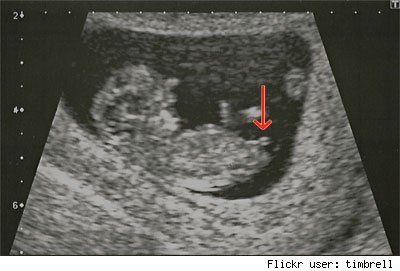

This is the split or fork nub

Attachment 9961